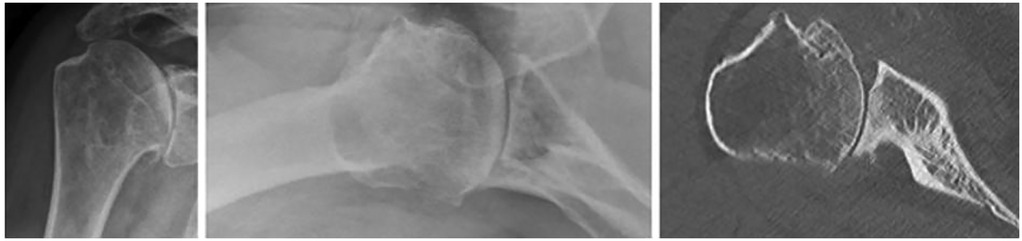

We used our institutional database of TSA procedures for this retrospective single-center study and included patients with a minimum radiological and clinical follow-up of 2 years after rTSA or aTSA for primary glenohumeral osteoarthritis with posterior glenoid wear classified as B2 or B3 according to Walch. To assess preoperative radiological features, all patients must have undergone a preoperative shoulder CT scan (Figure 1). Sixty patients met the inclusion criteria and were included in the study (Table 1).

Figure 1. Representative example of shoulder radiographs and CT scan in a patient with primary glenohumeral osteoarthritis and B2 glenoid wear.